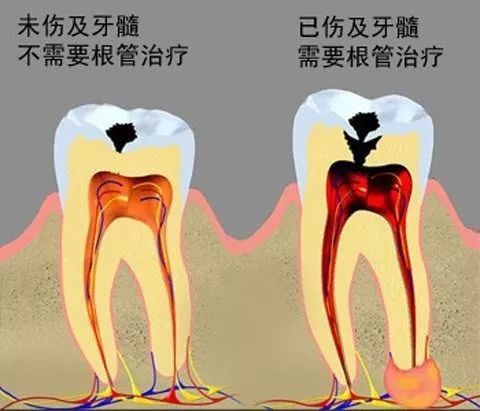

第一係蛀牙會痛,解釋係牙髓受細菌感染,可能已經導致牙髓炎,嗰陣要進行根管治療;

第三階段:牙齒超過一半爛曬,係話已經重度蛀牙,細菌傷及牙髓牙神經,仲伴隨住劇烈疼痛,牙神經病變就要番啲根管治療處理,拯救滿身傷痕嘅牙齒。

如果唔進行及時治療,病變就會愈來愈大,由淺蛀發展到深蛀,對凍熱酸甜等食物刺激敏感;當損傷到達牙髓,引發牙髓炎,呢個時候牙痛會好嚴重;病變再進一步發展,會引發根尖炎、根尖周膿腫,甚至顎骨骨髓炎,牙齒脫落失位。牙齒出事、冇啦,會影響嚼食,加重胃腸負擔,再者影響身體健康。

⊙牙齒受損之後,如果唔即時補牙,會造成牙膜位露,引發牙膜病。補牙可以防止病情繼續發展,重建患牙健康,防止牙髓炎、根尖周疾病發生。